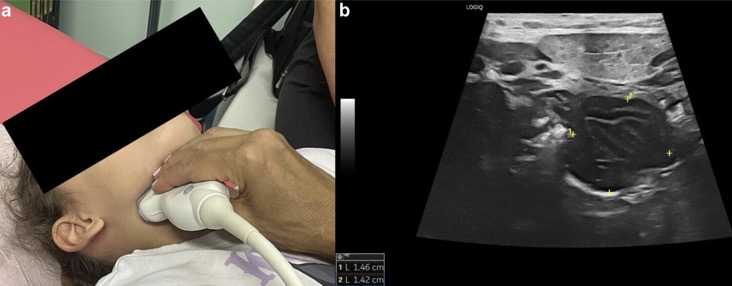

PATHOLOGIES INFLAMMATOIRES

EX: LYMPHOME DE BURKITT